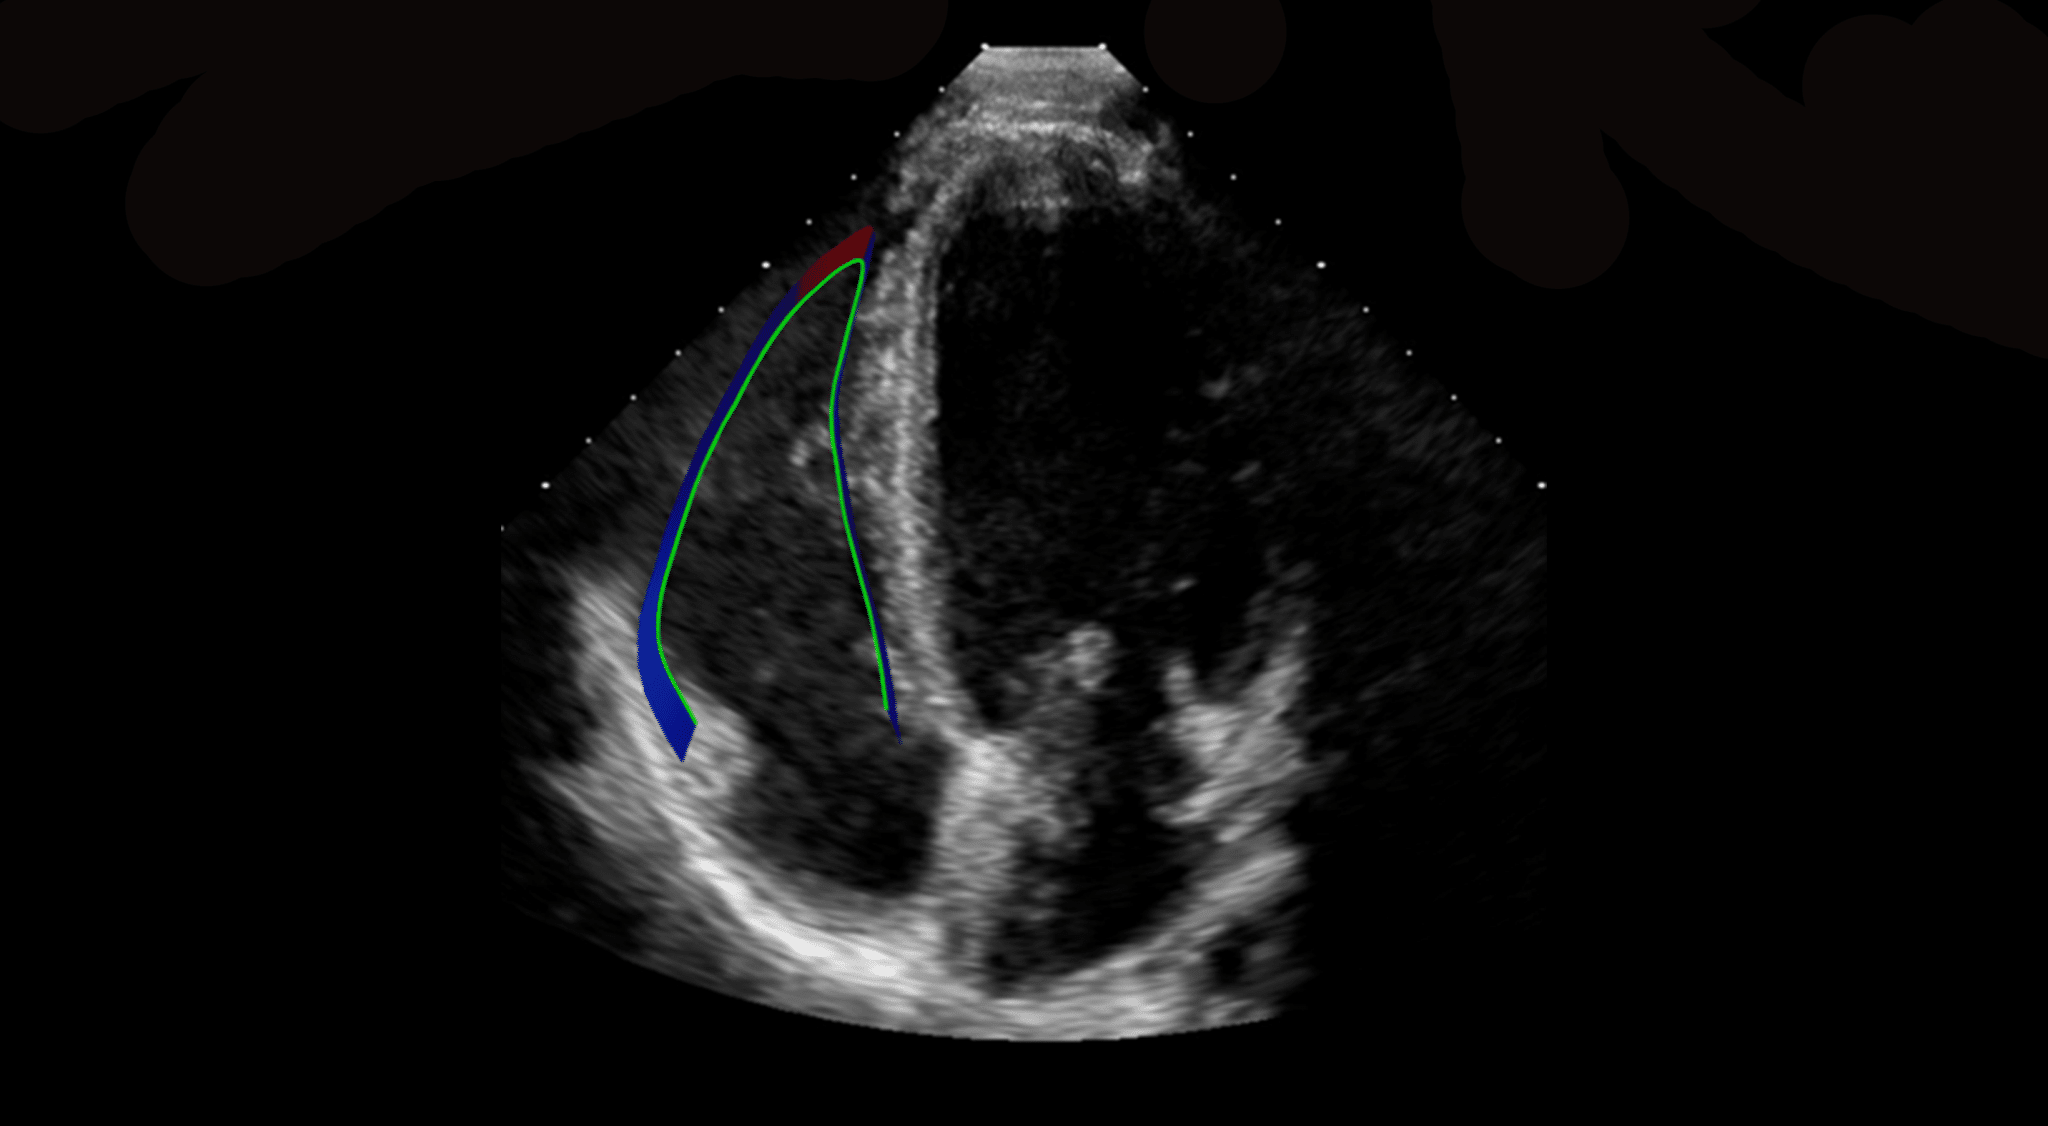

- Allows the quantitative evaluation of the Left Ventricle, Right Ventricle and the Left Atrium OEM solution. See the applications below for further details